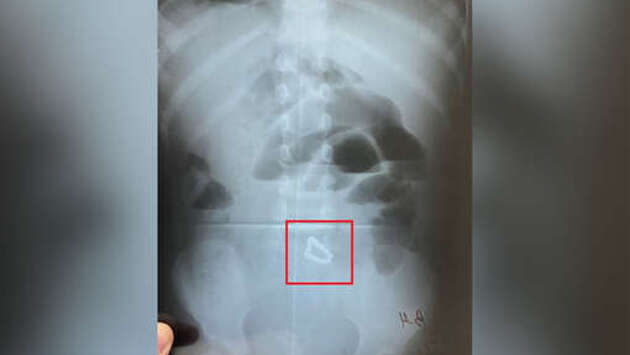

Хирурги больницы скорой помощи Уфы оказали помощь малолетнему ребенку, который наглотался магнитных шариков, потребовалось хирургическое вмешательство. Об этом сообщает минздрав Башкирии. Двухлетняя девочка поступила в медицинское учреждение с жалобами на вялость и многократную рвоту. В ходе обследования врачи обнаружили в кишечнике ребенка скопление инородных тел. "Девочку экстренно направили на операцию. Хирургическое извлечение инородных тел заняло два часа. Соединившись между собой в разных отделах кишечника, шарики спровоцировали его непроходимость и образование кишечных свищей", — сообщили в минздраве. Все 17 магнитных шариков от детского конструктора удалось извлечь, жизни и здоровью ребенка ничего не угрожает. Маленькая пациентка продолжает лечение в отделении реанимации. До этого сообщалось, что в Татарстане дошкольник разгрыз ртутный градусник и оказался в больнице. Двухлетний ребенок болел простудой и находился дома с бабушкой. Когда пожилая женщина отвлеклась, ее внук разгрыз прибор и проглотил несколько шариков металла. О своих "приключениях" дошкольник рассказал матери, когда вечером пришла с работы. Шарики вышли самостоятельно, что подтвердила повторная диагностика.